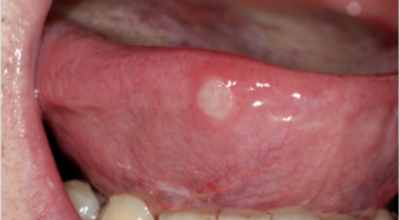

피부에 발생되는 편평 태선등의 것으로 자가면역질환의 한 가지로 알려져 있습니다. 주로 유전적인 까닭 및 면역 반응의 이상으로 나타나는 구내염으로 거미줄처럼 실선이 얽기 설기는 형태로 구내염이 발생해요. 발생 까닭이 명확하지 않아 치료가 어려우나 스테로이드 연고제를 통해 증상을 완화할 수 있습니다. 이런 형태의 구내염이 긴 시간 지속될 경우 구강암으로 발전할 수 있기 때문에 반드시 병원에서 진료를 받아봐야 해요.